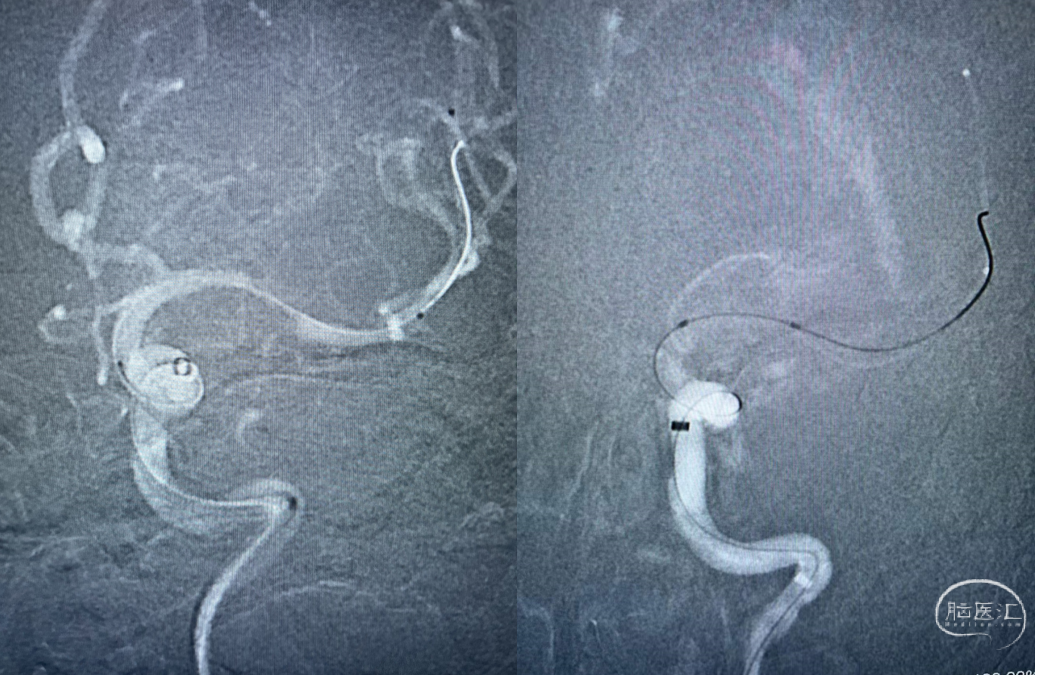

麻醉满意后,造影明确患者为Ⅲ型弓,血管迂曲,行左侧锁骨下造影示:左侧椎动脉开口处轻度狭窄,狭窄率约30%,超选入左椎动脉,造影示:左椎动脉及基底动脉走形正常,基底动脉、双侧大脑后动脉及小脑上动脉通畅,走形正常,前向血流TICI 3级。左颈总动脉及左侧颈内动脉走形正常,左侧大脑中动脉M1闭塞。撤出造影管。

术中DSA:左侧颈内动脉正侧位,M1闭塞

ASAHI微导丝携带Navien-72及SL-10微导管,造影血管通畅,前向血流缓慢,给予Gateway 2.0mm×15mm球囊球扩